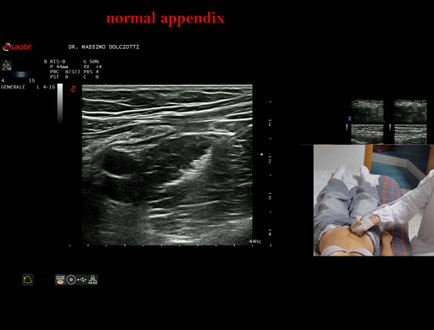

Data inserimento: 10/05/2023

Ecografia del: 05/05/2023

Strumento: Esaote MyLab Eight

Sonda: Lineare Multifrequenza 4-15 MHz

Età Paziente: M 21 anni

Motivazione dell'esame: dolori addominali.

Commento all'esame: le immagini ed il video documentano, in sede ileo-cecale, l'appendice di spessore e stratificazione regolare.

Conclusioni: appendice normale (normal appendix).

Presentazione: Dr. Massimo Dolciotti - Ancona

Elaborazione digitale: Andrea Dini - Ancona